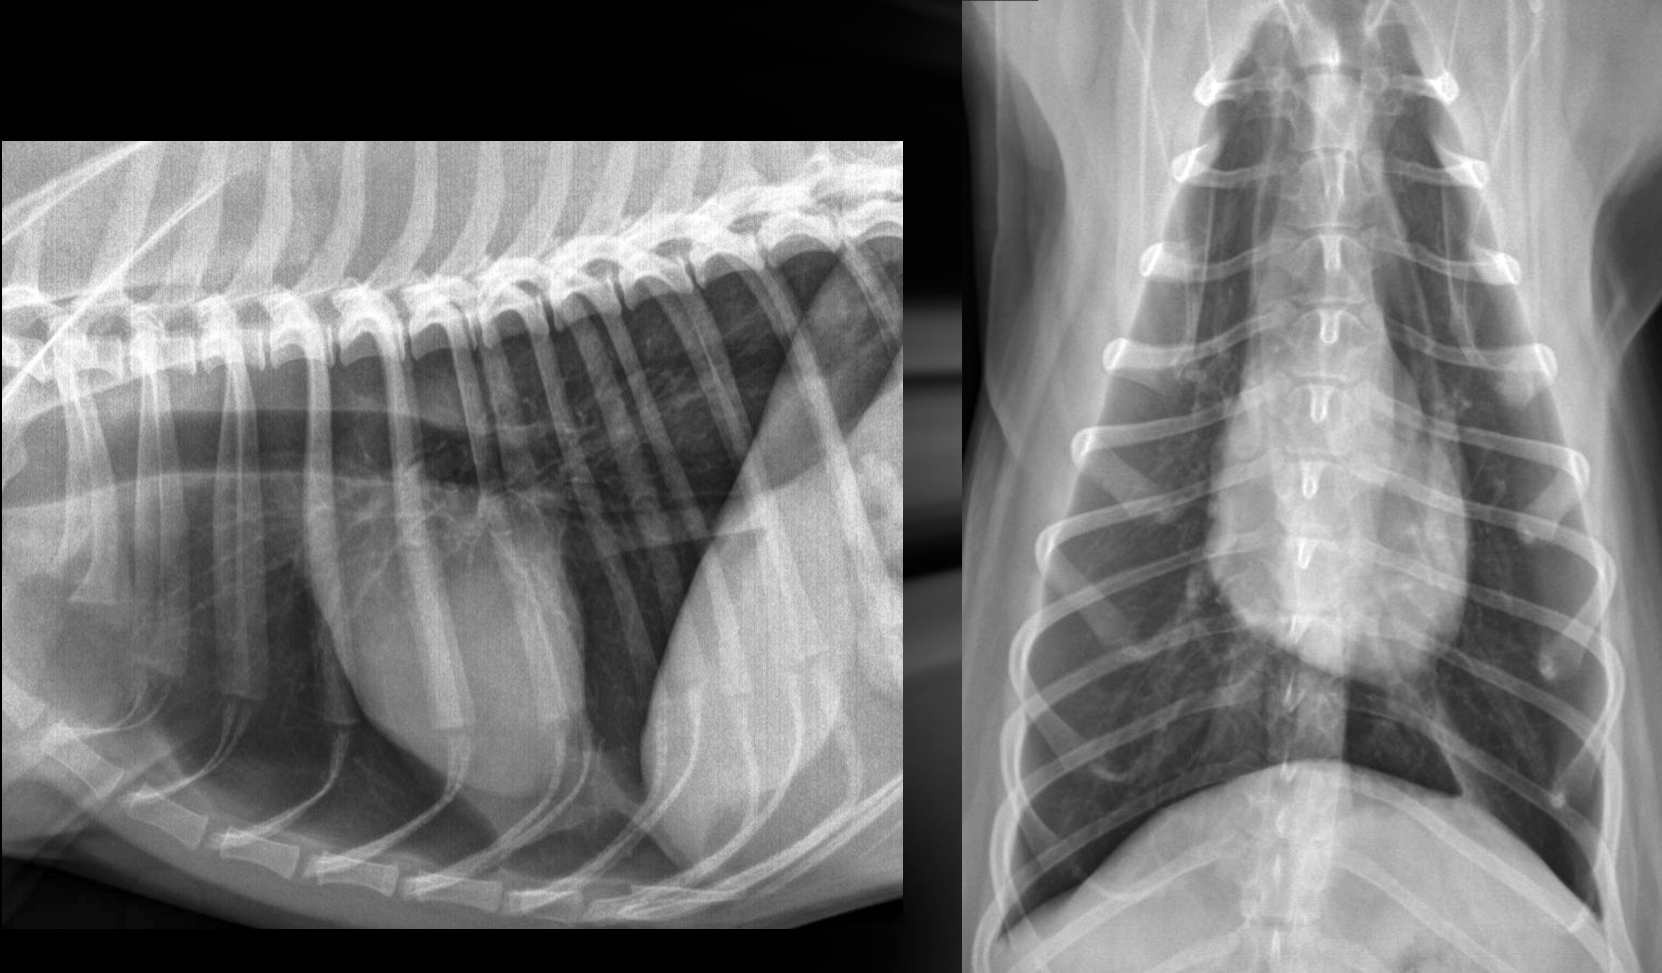

Roentgen signs of DCM

-Generalized cardiomegaly

± LHF > RHF or biventricular heart failure

-unstructured interstitial to alveolar in cd.dorsal